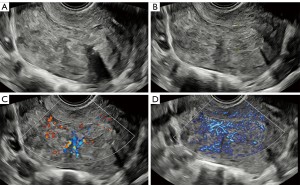

Figures 4,5 show the typical ultrasonic images of a nonmalignant endometrium. Figure 4 depicts the ultrasonic images of endometrial hyperplasia. The vascularity in the endometrium was scored higher on MVFI (score =2) than on CDI (score =1). Figure 5 provides ultrasonic images of endometrial polyps. The vascularity in MVFI was more abundant (score =4) than that in CDI (score =3).

Abundant vascularity was observed in endometrial malignancy, as depicted in Figures 6,7. Specifically, Figure 6 shows the high vascularity in focal atypical hyperplasia. The subjective score was higher for MVFI (score =4) than for CDI (score =2). A similar outcome can be observed in Figure 7, which shows endometrioid adenocarcinoma. CDI showed moderate vascularity (score =3), while MVFI showed abundant vascularity (score =4). MVFI exhibited more abundant vascularity in both nonmalignant and malignant endometria as compared with CDI.